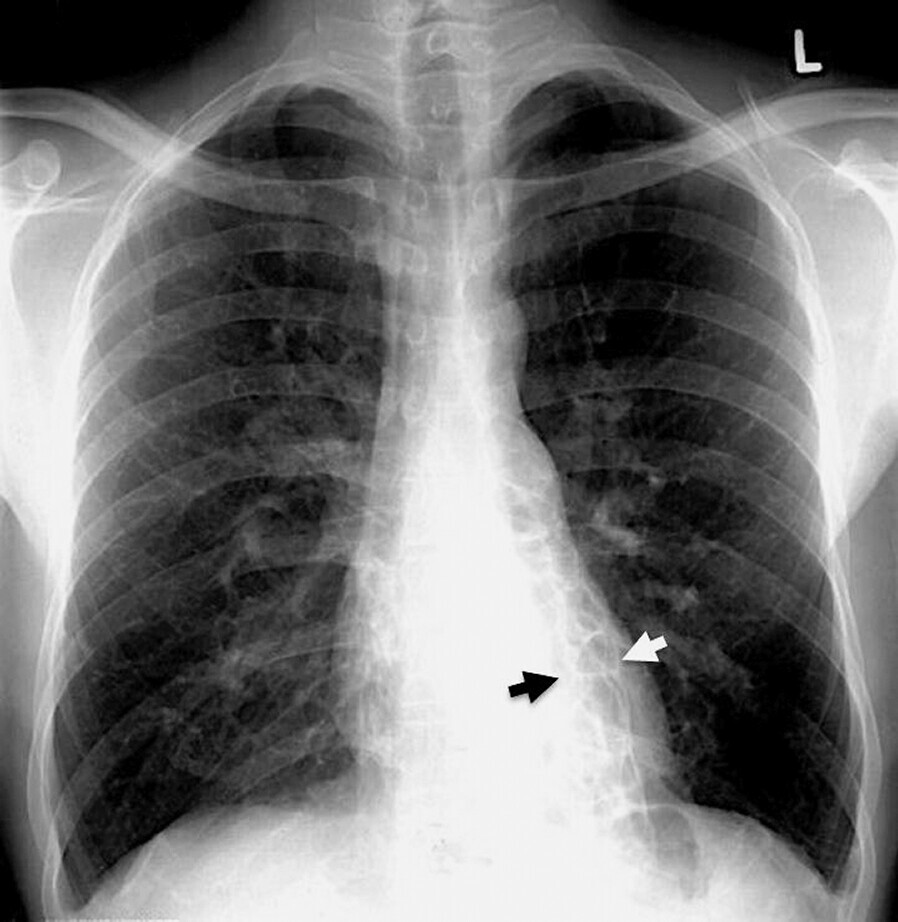

Im konventionellen Röntgenbild finden sich Hinweise auf Bronchiektasen (Abb. 75.2), (Tab. 75.2):

- verdichtete, verdickte Bronchialwände, Bild der „dirty chest“

- Narbenzüge, vereinzelte Dystelektasen

- parallele Streifenzeichnung („Straßenbahngleise“)

- zystische Hohlräume, z.T. mit Spiegelbildung

- lokalisierte Pleuraverdickung

- Infiltrate mit eingeschlossenen Hohlräumen

- in 5–10% der Fälle normales Röntgenbild

Abb. 75.2 Bronchiektasen im Röntgen-Thorax.

32-jähriger Mann mit kongenitalen sakkulären Bronchiektasen in beiden 10er-Segmenten. Die verbreiterten Bronchialsäcke und verdickten Bronchialwände lassen sich durch den Herzschatten als „netzwerkähnliche“ Strukturen erkennen (links > rechts, Pfeile). Nebenbefundlich sind die kostodiaphragmalen Winkel aufgrund rezidivierender Infektionen mit Begleitpleuritis verplumpt.

(Quelle: Kroegel C. Bronchiektasen. In: Kroegel C, Costabel U, Hrsg. Klinische Pneumologie. 1. Auflage. Stuttgart: Thieme; 2013. DOI: 10.1055/b-002-57146)